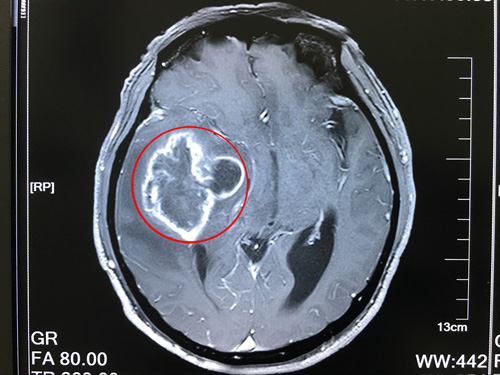

患者术前核磁影像:右侧颞叶占位,右侧高颅压,大脑镰疝

薛老汉有一个远房亲戚在上海工作,听说了他的事之后,就建议家属将薛老汉带到上海来治疗。和女儿一起来到上海之后,薛老汉先到上海某知名大医院做了详细检查。结果显示右侧颞叶占位病变,很有可能是胶质瘤。

到院后,沈建康教授接待了薛老汉,看了他的影像资料,询问了病史病情后,安排他完善了相关检查。患者住院后,沈教授将患者的病情,手术预后、以及风险和家属做了沟通。他说:胶质瘤是恶性肿瘤,现在患者的胶质瘤已属于3-4级,非常高危,如果不及时做手术,后果将不堪设想。